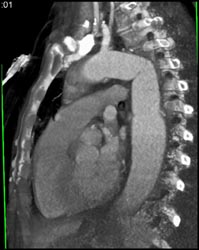

Diagnosis

Post Arch Repair